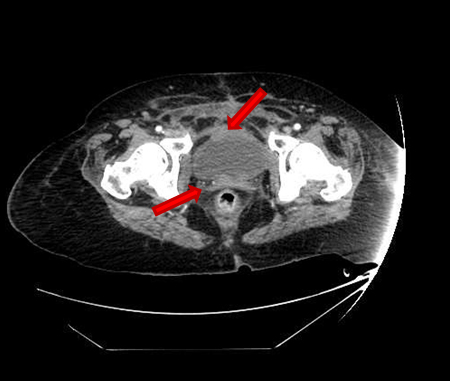

She presented on Emergency room suffering from fever, pelvic pain, and functional impairment of her right lower limb. Physical examination revealed bad smell vaginal flow and loss of strength on her right lower limb. Contrast computerized tomography and magnetic resonance images showed pelvic muscles impairment (Figure 1), inflamed bladder (Figure 2), and pelvic abscess lying from right psoas muscle to pubis bone, which presented radiologic signs of osteomyelitis (Figure 3) and (Figure 4).

Figure 1: CT scan image. Severe myositis of bilateral adductor, obturator, pectineus, and rectus abdominis muscles.